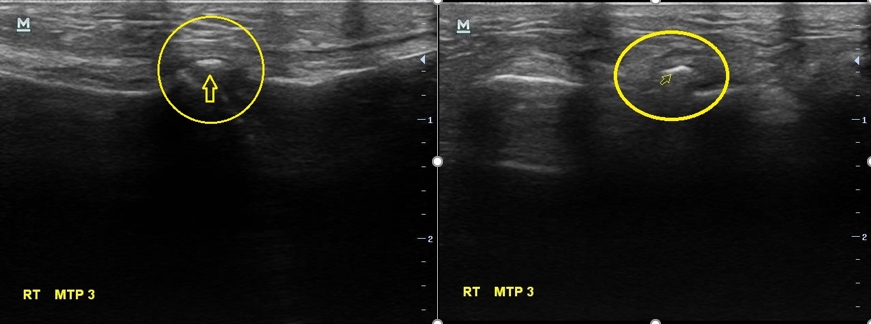

나 : X-ray는 괜찮은데요... 초음파에서 문제가 보이네요.

나 : 초음파에서 여기 하얗게 보이는거 있죠?

여성 : 네 보이네요...

나 : 이건 둘 중 하나인데요.... 첫번째는 금이 갔던 흔적인데.... 다친적은 없다고 하셨으니... 제 생각엔 석회 조각인거 같네요

나 : 네 석회성 건염이라고 해서 관절이나 힘줄 부위에 석회 조각이 생기고 이게 갑자기 염증을 만드는 경우가 가끔 있습니다.

이 여성의 병명은 '석회성 건염'이었습니다. 석회성 건염이라는 것은 우리 몸 관절부위에 석회가 쌓이면서 덩어리를 만들고 이게 염증을 만들어서 통증이 발생하는 병을 말합니다.